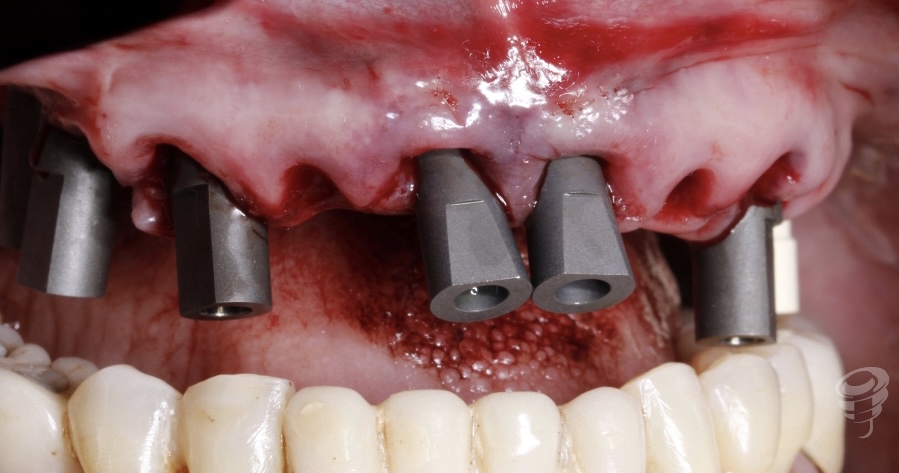

Posterior a la colocación de implantes, tomamos medidas digitales con scanbody.

Figura 6

1er provisional carga inmediata de 14 a 25 sobre 4 implantes.

Figura 7